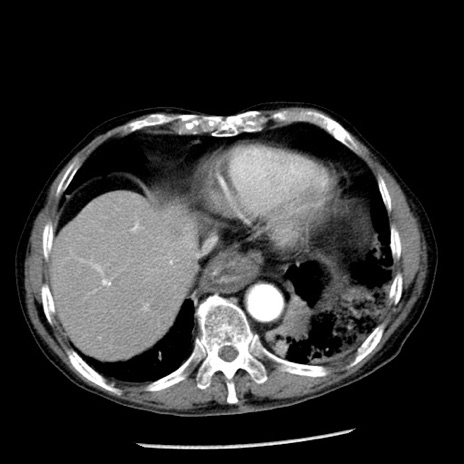

症例26(横断像)

【症例】80歳代男性

【主訴】嘔吐

【現病歴】昨晩2回嘔吐あり、今朝になっても嘔吐あり。来院。

【既往歴】胃潰瘍

【身体所見】意識清明、BT 37.6℃、BP 166/95mmHg、HR 100bpm、SpO2 97%、腹部:平坦・軟、腸蠕動音聴取良好、圧痛なし。

【データ】WBC 21900、CRP 1.46